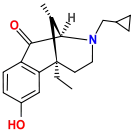

Benzomorphans

- 5,9 alpha-diethyl-2-hydroxybenzomorphan (5,9-DEHB)

- 8-Carboxamidocyclazocine (8-CAC)

- Alazocine

- Anazocine

- Bremazocine

- Butinazocine

- Carbazocine

- Cogazocine

- Cyclazocine

- Dezocine

- Eptazocine

- Etazocine

- Ethylketazocine

- Fedotozine

- Fluorophen

- Gemazocine

- Ibazocine

- Ketazocine

- Metazocine

- Moxazocine

- Pentazocine

- Phenazocine

- Quadazocine

- SKF-10047

Structures

| Benzomorphans | ||||

|---|---|---|---|---|

5,9 alpha-diethyl-2-hydroxybenzomorphan 5,9 alpha-diethyl-2-hydroxybenzomorphan (5,9-DEHB) |

8-Carboxamidocyclazocine 8-Carboxamidocyclazocine |

Alazocine Alazocine |

Anazocine Anazocine |

Bremazocine Bremazocine |

Butinazocine Butinazocine |

Carbazocine Carbazocine |

Cogazocine Cogazocine |

Cyclazocine Cyclazocine |

Dezocine Dezocine |

Eptazocine Eptazocine |

Etazocine Etazocine |

Ethylketocyclazocine Ethylketocyclazocine |

Fedotozine Fedotozine |

Fluorophen Fluorophen |

Gemazocine Gemazocine |

Ibazocine Ibazocine |

Ketazocine Ketazocine |

Metazocine Metazocine |

Moxazocine Moxazocine |

Pentazocine Pentazocine |

Phenazocine Phenazocine |

Quadazocine Quadazocine

|

Thiazocine Thiazocine |

Tonazocine Tonazocine |

Volazocine Volazocine |

Zenazocine Zenazocine |

|||